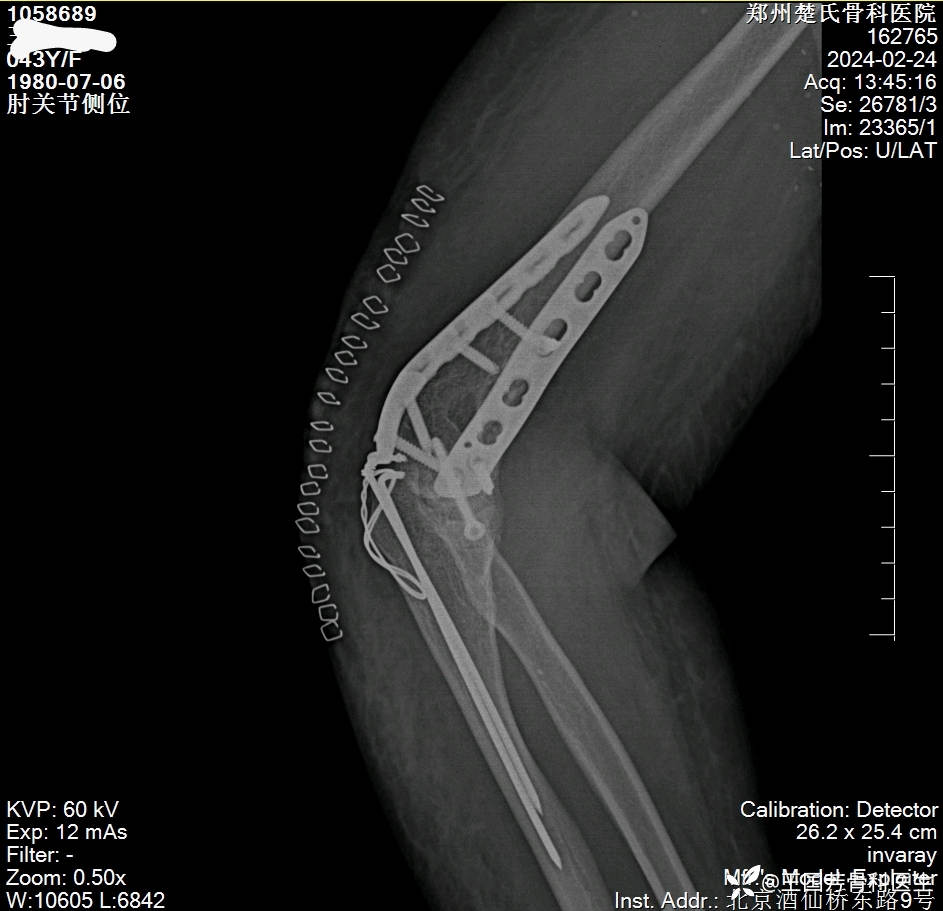

女,43岁,摔倒致右肘肿痛伴活动受限2小时入院。

诊断:肱骨髁间粉碎性骨折

伸直型损伤

Radjn分型:IV型

术后DR、CT